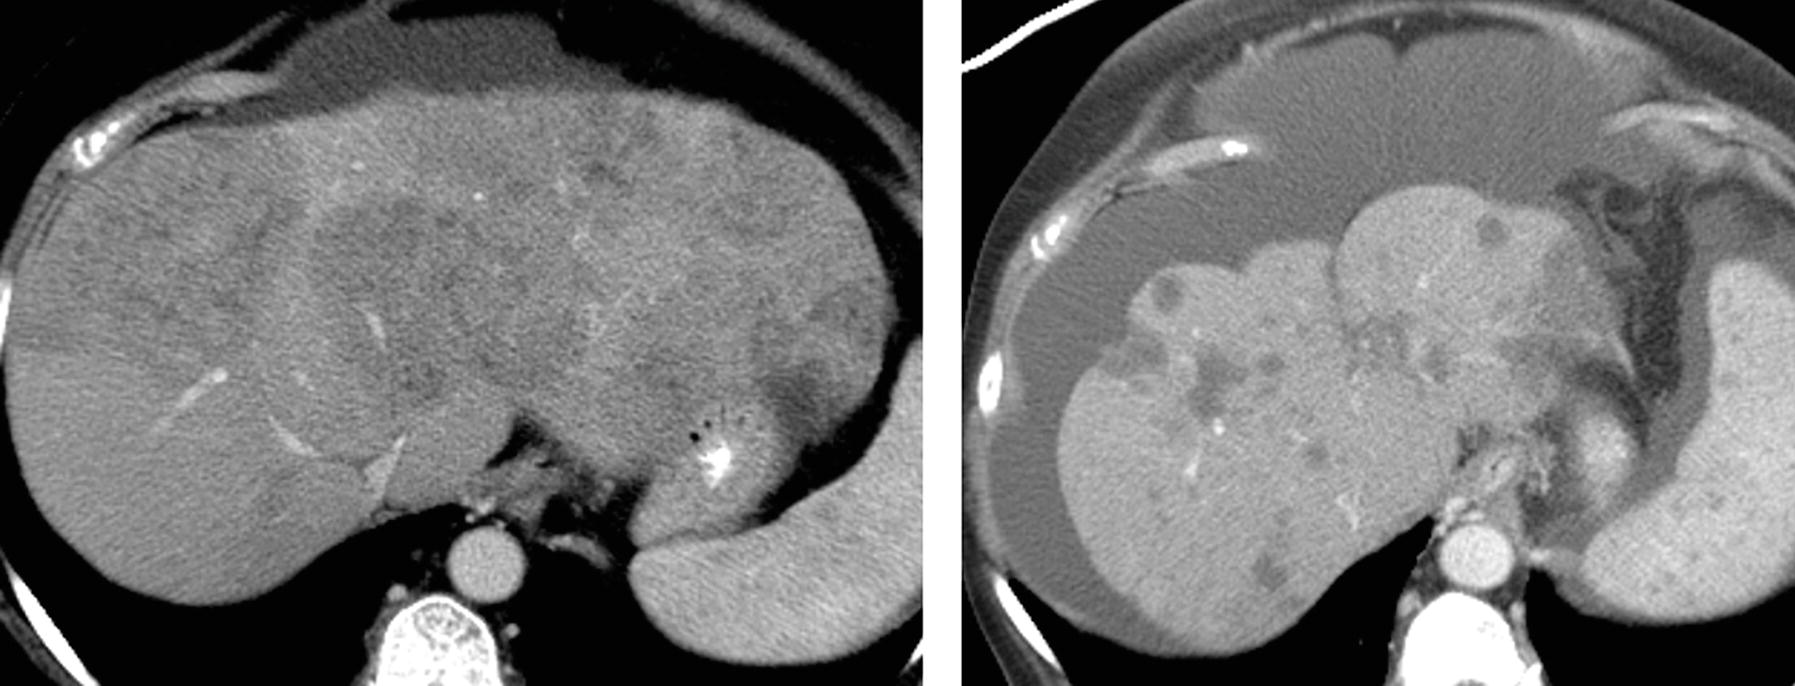

A 56yearold patient with a case of nutmeg liver. Axial and coronal Nutmeg Appearance Of Liver Radiology The liver shows heterogeneous enhancement with periportal edema and dilated hepatic veins, however, the portal and hepatic. Radiologically, it is most appreciable on. Radiologically, it is most appreciable. Nutmeg liver refers to the mottled appearance of the liver as a result of hepatic venous congestion. Nutmeg liver refers to the mottled appearance of the liver as a result of hepatic. Nutmeg Appearance Of Liver Radiology.

Nutmeg Appearance Of Liver Radiology . Nutmeg liver refers to the mottled appearance of the liver as a result of hepatic venous congestion. Radiologically, it is most appreciable on. Nutmeg liver refers to the mottled appearance of the liver as a result of hepatic venous congestion. The liver shows heterogeneous enhancement with periportal edema and dilated hepatic veins, however, the portal and hepatic. Radiologically, it is most appreciable. Nutmeg liver refers to the mottled appearance of the liver as a result of hepatic venous congestion. The changes in hepatic vasculature lead to hepatic venous congestion and perfusion abnormalities most prominent in the liver periphery manifesting in a nutmeg liver appearance on computed tomography (ct) scan. Nutmeg liver refers to the mottled appearance of the liver as a result of hepatic venous congestion. Radiologically, it is most appreciable. Recognition of passive hepatic congestion on ct or mri may help explain liver function. Radiologically, it is most appreciable on.